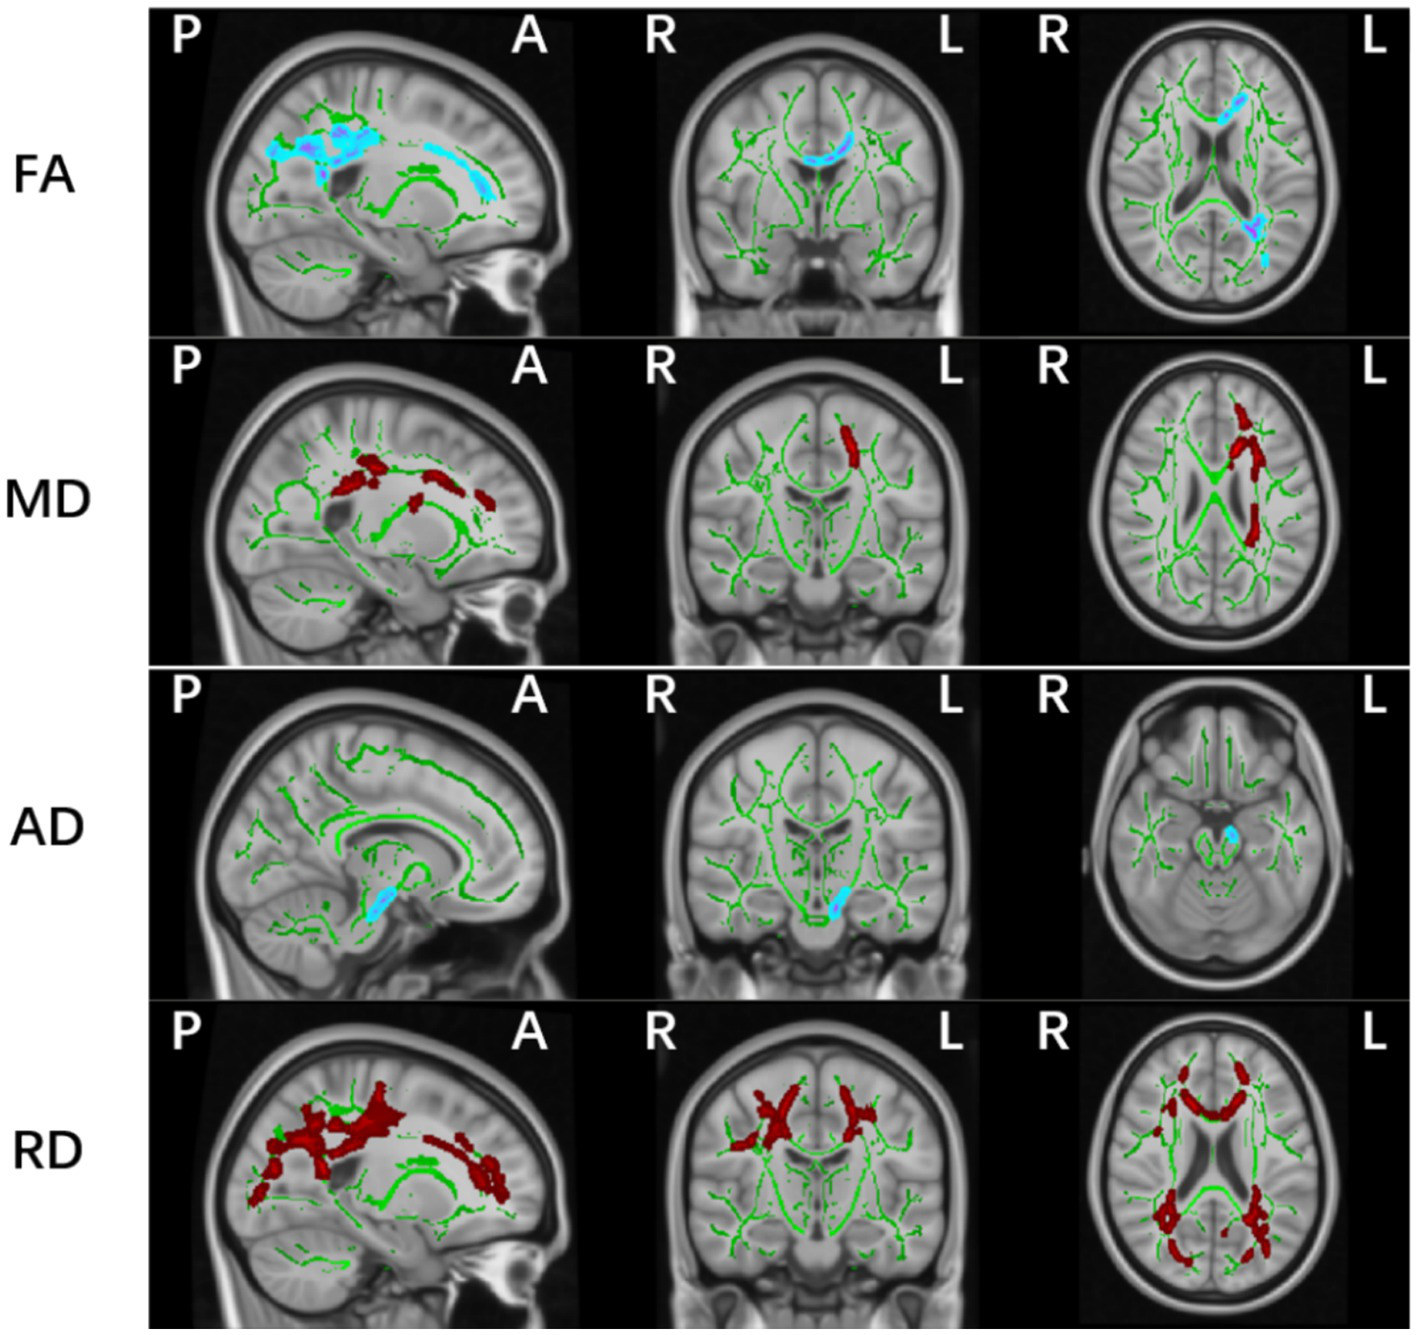

Whole-brain TBSS analysis of DTI data revealed statistically significant white matter differences in multiple parameters (FA, MD, AD, and RD) between the PD-MCI and HC groups (p < 0.05, TFCE corrected; Table 2 and Figure 2). The affected regions were as follows:

-

FA (Fractional Anisotropy):

Significant decreases were observed in the corpus callosum (including the genu, body, and splenium), the left anterior, superior, and posterior corona radiata, and the left posterior thalamic radiation (including the optic radiation).

MD (Mean Diffusivity):

Increased MD values were detected in the corpus callosum (genu and body), the left anterior, superior, and posterior corona radiata, the left retrolenticular part of internal capsule, the left posterior thalamic radiation (including the optic radiation), and the superior longitudinal fasciculus.

AD (Axial Diffusivity):

Significant differences were identified in the left corticospinal tract and cerebral peduncle.

RD (Radial Diffusivity):

Affected regions included the corpus callosum (genu, body, splenium), bilateral anterior, superior, and posterior corona radiata, bilateral superior longitudinal fasciculus, posterior thalamic radiation (including the optic radiation), the right sagittal stratum (including the inferior longitudinal fasciculus and inferior fronto-occipital fasciculus), and the left retrolenticular part of internal capsule.

Figure 2

Significant white matter differences between PD-MCI and HC groups (p < 0.05, FWE controlled). FA, fractional anisotropy; AD, axial; MD, mean and RD, radial diffusion. The background image is the standard MNI152 brain template. Green voxels represent the white matter skeleton of all subjects; Red colors denote decreased and blue colors increased cortical thickness in patients compared with controls; L, left; R, right; (P), posterior; (A), anterior.

No significant differences were observed in FA, MD, AD, or RD values between the PD-NC and HC groups, or between the PD-MCI and PD-NC groups.